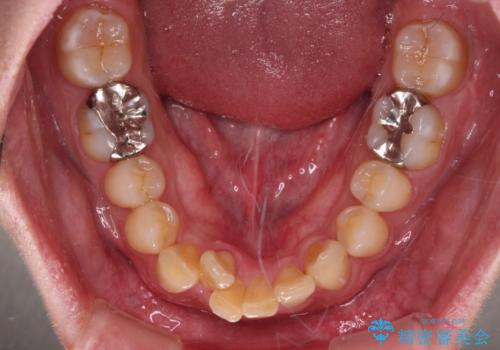

- 深い咬み合わせによる食いしばりで、顎関節や頭が痛むことがあるとのことで来院された患者様です。

歯ぎしりができないくらい強い食いしばりの咬合状態であったため、奥歯の歯軸を起き上がらせることで咬合を挙上させ、歯ぎしりができるようにしていくこととしました。

下顎が左側にずれているため、上下正中は最大限合わせられるところまで合わせるゴールとなりました。